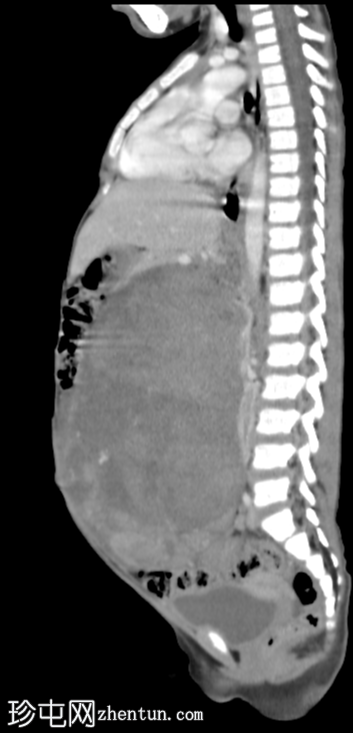

矢状位增强扫描(门静脉期)

CT扫描显示左侧腹盆腔内存在一个较大的、部分边界清晰、呈不均匀强化的软组织密度肿块。肿块后方与左肾无法分离。

肿块对邻近器官有明显的压迫作用。

右肾外观未见异常。

CT

影像

学表现符合左侧

肾脏

肿块,

病理

证实为肾母细胞瘤。